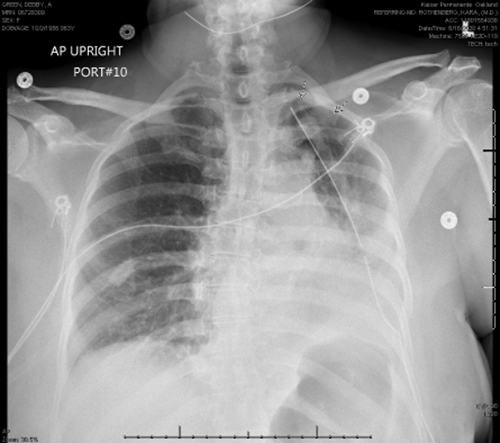

A routine chest X ray on postop day (POD) 1 showed appropriate reinflation of the lung (Figure 1), and the chest tube was removed. She had persistent pain and a brief episode of atrial fibrillation on POD 1-2 and thus remained inpatient for ongoing treatment monitoring. On POD 3, she developed progressively worsening hypoxia with rapid progression, requiring BiPAP with 80% O2 to maintain oxygen saturation >90%. A chest radiograph was obtained, and when compared to the imaging on POD 1, it revealed near whiteout on the left side (Figure 2).

Figure 2. Chest Radiography on POD 3, Revealing Significantly Worse Aeration and “Whiteout” of Remaining Left Lower Lobe. Published With Permission